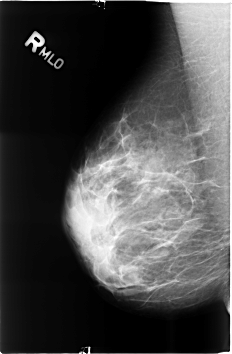

B_3497_1.RIGHT_MLO

RIGHT_MLO LINES 4600 PIXELS_PER_LINE 3008 BITS_PER_PIXEL 12 RESOLUTION 50 NON_OVERLAY